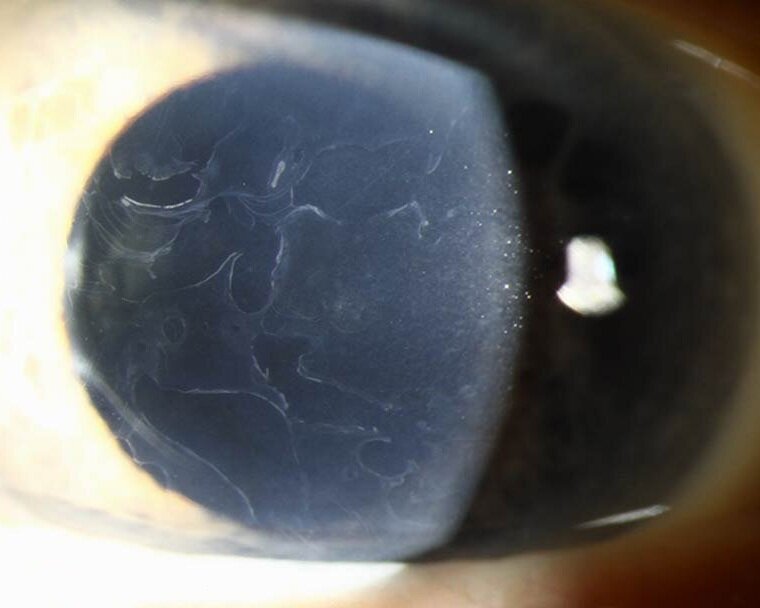

Имеет аутосомно-доминантный тип наследования (ген TGFBI, локус 5q31), билатеральная, симметричная. Заболевание проявляется в первую декаду жизни. Осмотр за щелевой лампой выявляет хорошо видимые гранулы, которые кажутся белыми при прямом освещении. При ретроиллюминации эти гранулы состоят из чрезвычайно мелких, полупрозрачных точек, выглядят как вакуоли, стеклянные осколки или измельченные крошки. Помутнения не захватывают лимбальную зону. У детей коричневые гранулы, образующие вихревидный рисунок, расположены относительно поверхностно и распространяются к слою Боумена. В дальнейшем гранулы простираются в глубокие слои стромы вплоть до десцеметовой мембраны. Блики и светобоязнь являются относительно ранними симптомами. Так как на начальных этапах регулярность передней поверхности не нарушена, острота зрения остается высокой. С возрастом помутнения прогрессируют, сливаются между собой, острота зрения постепенно снижается. Иногда имеют место рецидивирующие эрозии. В развитых стадиях острота зрения редко снижается менее 0,1. Как правило, к 50-60 годам необходима кератопластика, после которой вероятны рецидивы в течение нескольких лет (от 1 года до 20 лет).